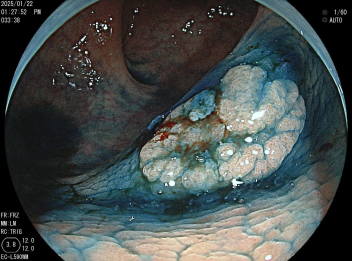

忙しかった奈良市の健診も終わりホッと一息というところです。たくさんの方に大腸癌検診も受けていただきましたが、中には要精密検査(便潜血陽性)になった方もおられることでしょう。そこで今回は大腸カメラの検査時期についてお話します。

まず便潜血陽性になった方は、過去3年以内に大腸カメラを受けていなければ大腸カメラを受けましょう。逆に大腸カメラを受けて3年以内の便潜血検査は基本的に不要です。次に目に見える血便があった場合ですが、たとえそれが痔だと思っていても大腸に病変が隠れている可能性があるので大腸カメラを受けるべきです。あとは便通異常のある方、癌マーカー(CEACA19-9など)が上昇している場合にも大腸カメラが推奨されます。また過去に大腸カメラを受けたことのある方については、2020年に発表された「大腸内視鏡スクリーニングとサーベイランスガイドライン」にもとづいてサーベイランス(2回目以降の検査)を行います。大腸にポリープがなかった場合、次回のカメラは510年後で良いでしょう。大腸ポリープ(腺腫)を取った方は3年後の大腸カメラが推奨されます。大腸ポリープが10個以上あった方、20mmを越えるポリープを取った方、早期大腸癌があった場合には1年後の大腸カメラが推奨されています。そして重要なのは、何もなくても過去に大腸カメラを受けたことのない方は、50歳を越えたら一度は大腸カメラを受けるということです。これはスクリーニング(初回検査)という概念に基づくもので、10年以上前から米国では「サーベイランスからスクリーニングへ」を最重視しました。これが米国で大腸癌が半減した最大の理由です。日本では大腸カメラの「サーベイランス(2回目以降)」は充足していても「スクリーニング(初回検査)」がまだまだできておらず、それが米国に比べて日本における大腸癌の発生数が減らない主な原因だと考えられています。大腸カメラは大量の下剤の服用が必要なこと、カメラ自体が苦痛であることなどからハードルが高い検査だと思われがちですが、昔よりはずいぶんと楽に受けられるようになっています。まだの方はぜひ一度は大腸カメラを受けてみましょう。